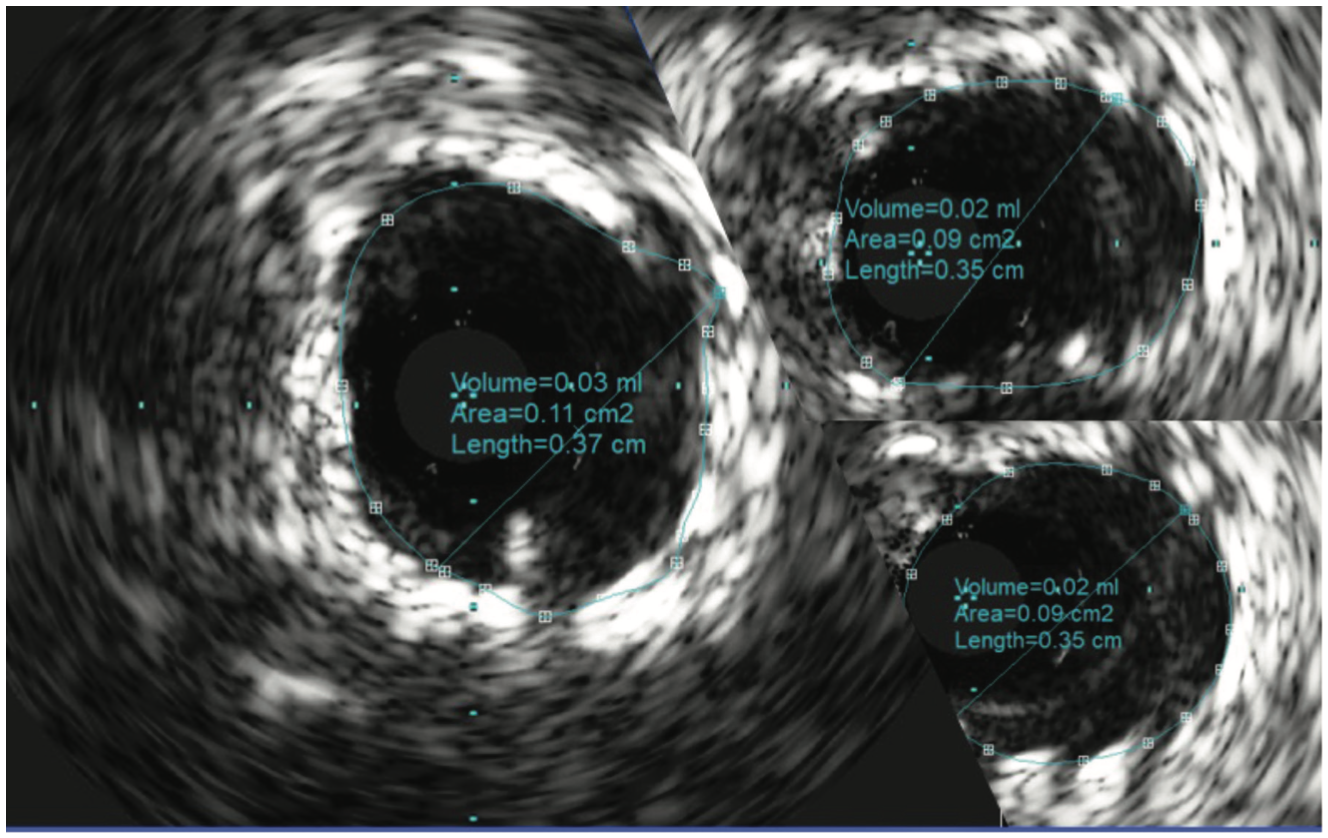

The patient’s electrocardiogram showed sinus rhythm with left bundle branch block and echocardiography demonstrated a normal left ventricular ejection fraction with a transvalvular aortic mean gradient of 10 mmHg. On further evaluation, his nuclear stress test showed severe anterior ischemia. A review of his previous angiograms demonstrated an underexpanded stent in the distal LM that was potentially constrained by a circumferential calcific lesion (Figure 1). Intravascular ultrasound (IVUS) and atherectomy were not utilized during the index procedure. The patient underwent cardiac catheterization via the right femoral approach, which demonstrated severe in-stent restenosis (ISR) of the distal LM due to an underexpanded/undersized stent (Figure 2), confirmed on assessment of the non-contrast chest imaging and IVUS, with a minimum stent area (MSA) of 4 mm2 (Figure 3). Given the patient was not a surgical candidate, further percutaneous management was elected as the best management strategy since the patient had refractory angina despite medical therapy. Mechanical support with large-bore access was not feasible, given the vascular disease in his lower extremities had worsened, and with severe carotid disease, the patient was not a candidate for axillary large-bore devices. He was pre-treated with aspirin and clopidogrel before the PCI.